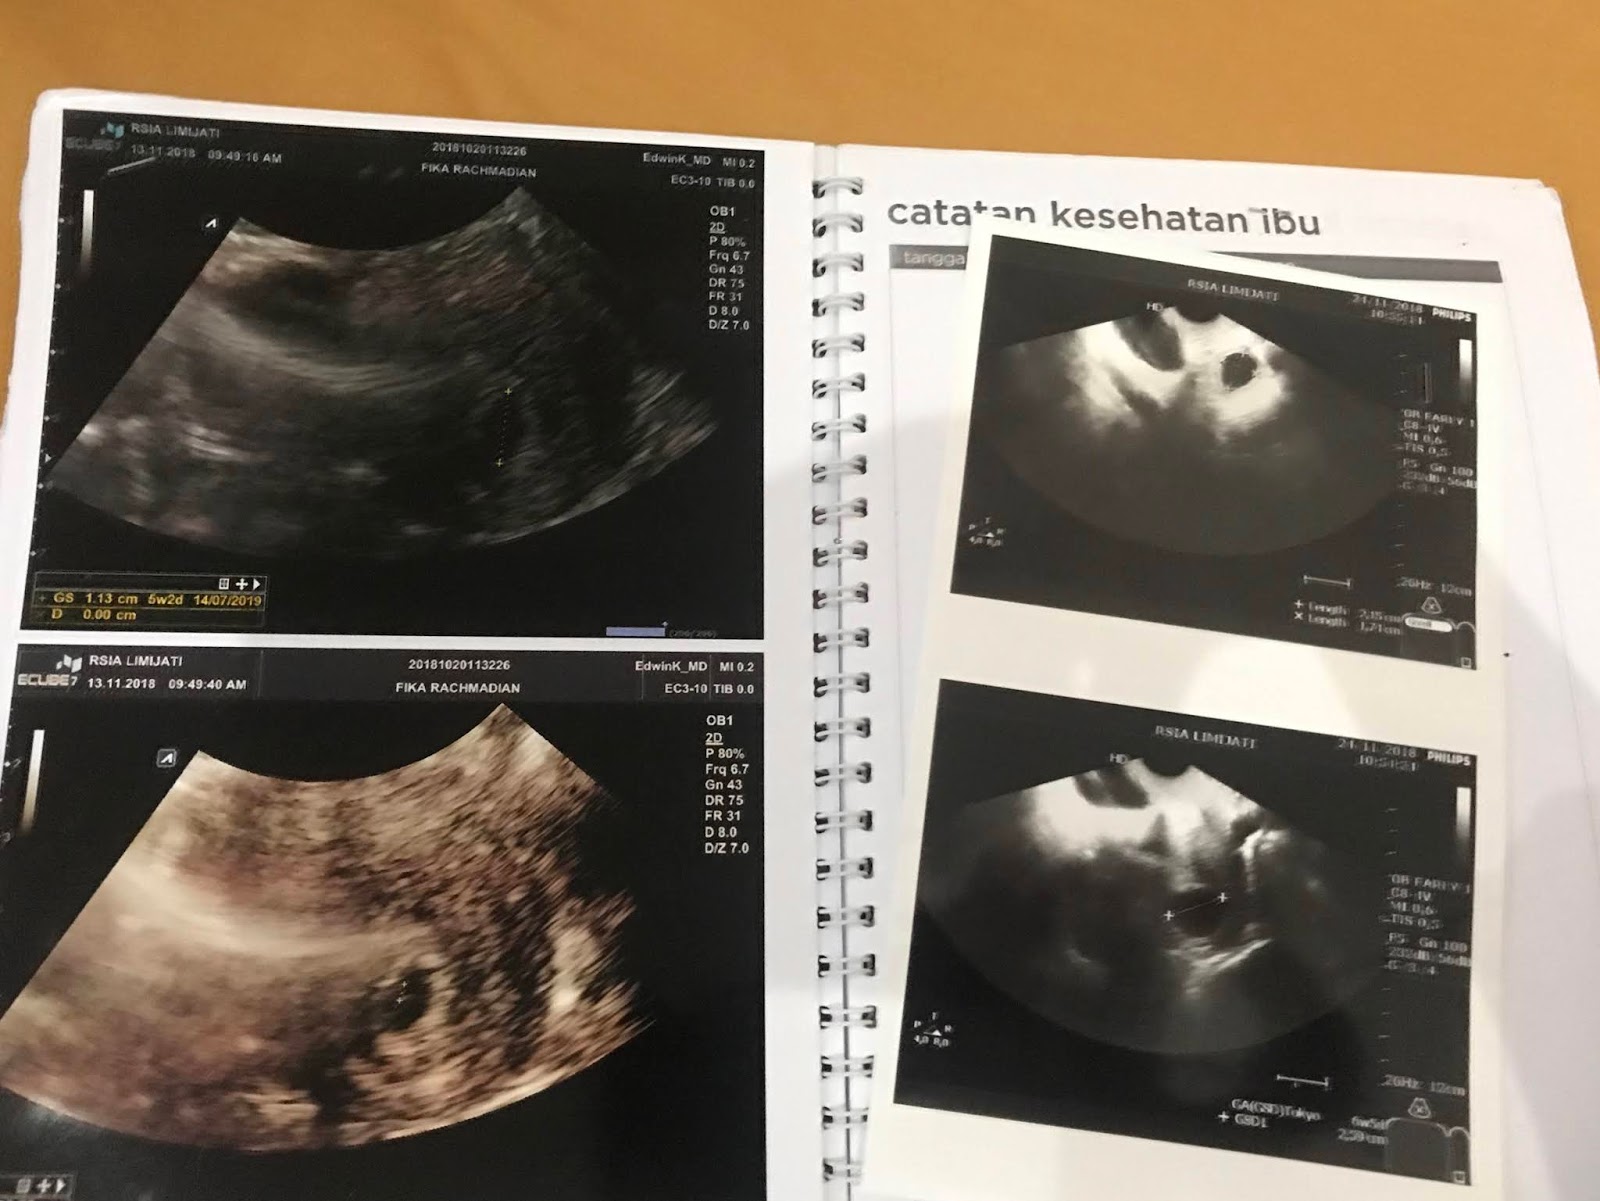

Gambar Usg Sel Telur Matang

BEGINI GAMBAR SEL TELUR YANG SUBUR… - dr Yudhistya SpOG | Facebook Story of My Journey: TTC Journey #2 USG Folikel dan Hasil Analisa Sperma Aku dan PCOS (Hasil USG Trans Vaginal) - JalanSenja.com Cerita Promil 4 - Polycystic ovary (PCO) - Fika Putri Cerita Promil 2 - USG Transvaginal dan Tes Sperma - Fika Putri Semua Akan Terjawab di Waktu yang Tepat - kumparan.com Promil Story : MIMPI BURUK ITU BERNAMA PCOs - The Arsalan Family Journal Penting Dilakukan Wanita, Ketahui Sel Telur Dalam Tubuhmu Jangan Sampai “Mandul” Karena Kehabisan Program Hamil di Dokter Lusiana Irene, SpOG Jogja Manusia sedikit tahu..sel telur kecil tidak mungkin hamil | Dr Suryo, SpOG - Kesehatan Reproduksi C e r i t a C i k i: Sel Telur Kecil-Kecil EFEK PENYUBUR Pada wanita normalnya sel… - dr Yudhistya SpOG | Facebook Ikhtiar yang ke dua – Part 2 (H6-H11) – Bread and Butter Letter Promil Step 4 – Baby Journey PCOS adalah… | Kisah Ibuknda (pakai ‘k’) :D Room | ‘Aisyah Tsurayya Inart’s Story - Yah, Saya Akhirnya Hamil - I’m 1 In 10: My PCOS Story Kisah Perjuangan Terbaru Tya Ariestya Saat Jalani Program IVF | Popmama.com story of my lyfe: pejuang keturunan Nikita Mirzani Bagikan Hasil USG Bayi Kembar, Dapatkah Gen Kembar Diturunkan? - Semua Halaman - Intisari lihat hasil USG tranvaginalku wktu bulan Januari 2013 apa itu PCO? - IbuHamil.com Cerita Promil 4 - Polycystic ovary (PCO) - Fika Putri aq PCO bund, ada yg bisa bantu baca hasil USG intravagina q??? - IbuHamil.com Hasil USG Sel Telur Yang Subur - YouTube Pengalaman Bayi Tabung/ IVF (Part II) Update with Pict! | honeymenulis’s Blog Inart’s Story - Yah, Saya Akhirnya Hamil - Story of My Journey: June 2017 Ingin Terhindar dari Kista? Jauhi 4 Jenis Makanan Enak Ini Sekarang! - Semua Halaman - Grid Health Program Hamil Bulan ke-1 : PCOS Survivor | Lanalouie Embrio 3 cm berapa minggu. minggu: bayi Anda sebesar tongkol jagung BEGINI GAMBAR RAHIM YANG SUBUR… - dr Yudhistya SpOG | Facebook PCOS | medicalstudentnotes USG Transvaginal: Penjelasan, Prosedur & Manfaat (Lengkap) | Friso BILIK SONOGRAFER : Kista Ovarium Kontrol H+10 (Cek Perkembangan Sel Telur) Istilah kehamilan dipertimbangkan dengan USG. Kehamilan kebidanan dan embrio Selamat Pagi Senin Ayah Bunda. Semoga… - Dokterkandungan. id | Facebook My First USG | Story of Us Menuju Hamil – Part 2 of 3 – Edward Suhadi Apa itu PCOS? Kenapa Sulit Hamil? | Sunshine of My Life Setiap Ibu Hamil Harus Tahu, Kapan Harus Melakukan USG lewat Vagina? - Semua Halaman - Nakita Program Hamil di Dokter Lusiana Irene, SpOG Jogja Saat Sel Telur Berukuran Kecil dan Sulit Dibuahi - Health Liputan6.com Kabar Gembira, Ini Tanda Awal Sel Telur Berhasil Dibuahi oleh Sperma | Popmama.com 101+ Gambar Cek Sel Telur Paling Hist - Gambar Pixabay Kontrol H+12 (Mendebarkan, apakah sel telurnya tetap berkembang?) Program Kehamilan Balasan dari Saya Penderita PCOS, Saya Berhasil Hamil | KASKUS Pembekuan Sel Telur: Fungsi, Prosedur, dan Komplikasi INGIN HAMIL – Siklus Ovarium dan Tanda-Gejala Wanita Subur | JuliantoWitjaksono.com 6 Fakta Mengejutkan Tentang Sel Telur Wanita - YouTube Pengalaman Hamil Kembar - The Urban Mama Maimuns — PCOS? Deal with it! Berapa Sisa Sel Telur di Tubuh? Bisa Dicari Tahu | Parenting.Dream.co.id PCOS Polycystic Ovary Syndrom Apakah… - Komunitas Impian Bunda | Facebook Persiapan Hamil (4) – jurnal Ammi Wanita Hasilkan 2 Sel Telur dalam Masa Ovulasi, Bisakah Terjadi? Promil Story : MIMPI BURUK ITU BERNAMA PCOs - The Arsalan Family Journal My journey to motherhood: HSG, Tes Sperma, hingga PCO Polikistik Ovarium (PCOS): Haid sering tidak datang, Berkumis, Berjerawat, Ingin hamil sulit | Dr Suryo, SpOG - Kesehatan Reproduksi PCOS dan Metformin. Sohib karib! – Cerita Bumi Blighted Ovum | ~cahaya kebaikan~ Cerita Pengalaman Kehamilan Pertama dan Persiapan Melahirkan Anak Pertama - For The Love of Foods and Beauty Masih banyak yg belum tau.. INSEMINASI… - Bayi Tabung PMC Pekanbaru Cerita Program Hamil dengan Dokter Enny Sp.OG di Yogyakarta ~ Land of Jenganten Semua Akan Terjawab di Waktu yang Tepat - kumparan.com Fika Putri Berbagi Tips: Cara Mengetahui Masa Subur Wanita Berdasar Penghitungan serta Ciri-Cirinya - Garda Remaja GAGAL OVULASI?? SERING TERJADI PADA… - Konsultasi Promil Cepat Hamil dan Alami | Facebook Yosevina Issabela prosespersalinan Instagram posts (photos and videos) - Picuki.com Apa sebetulnya bayi tabung dan bagaimana proses menjalaninya? – Bayi Tabung Penang Di minggu kebidanan mana embrio terlihat. Minggu berapa embrio terlihat pada USG? Apakah prosedurnya aman pada tahap pembentukan anak PCOS itu Variable dan Sangat Rumit Prosedur Bayi Tabung: Sebelum dan Sesudah Mengikutinya - Smarter Health Mengenal Kehamilan Kosong atau Blighted Ovum (BO) - Kompasiana.com Cerita Promil, Perjalanan menuju kehamilan (long story short, I finally got pregnant) - Nyonyah Intan Sindrom Ovarium Polikistik (PCOS) 4D Gallery | Dr Suryo, SpOG - Kesehatan Reproduksi Kapan USG direncanakan selama kehamilan. Apakah saya perlu mempersiapkan prosedur? Keadaan organ reproduksi wanita Irish Bella Hamil Anak Kembar, Sang Ibunda Tak Sangka Bakal Punya 2 Cucu - Halaman all - Tribun Batam Lapsus Kista Ovarii - Apriamalia - [PDF Document] Success story – GLADIOOL IVF RS Indosehat Solo, Jl Solo Sragen Km 11, Kebakramat, Karangdawa (2020) Saya Penderita PCOS, Saya Berhasil Hamil | KASKUS September 2014 - Pipit Widya Aku dan PCOS (Hasil USG Trans Vaginal) - JalanSenja.com Pengalaman PCOS-ku yang Berhasil Hamil Alami - kumparan.com Apakah USG mempengaruhi kehamilan. Bagaimana ultrasound mempengaruhi embrio? Ultrasonografi dilakukan hanya atas kesaksian dokter atau mungkin atas permintaan ibu BAB III - [DOCX Document] Kista Ovarium. - ppt download Biaya USG 3 & 4 Dimensi di Karawang - Perawatan Kesehatan Cerita Pengalaman Kehamilan Pertama dan Persiapan Melahirkan Anak Pertama - For The Love of Foods and Beauty Wanita Punya 400 Sel Telur Setiap Menstruasi, Kenapa Susah Hamil? - Semua Halaman - Nakita Tragis Si Ibu Hamil Dibunuh, Bayi di Dalam Kandungan Dicuri - Halaman all - Warta Kota Perlukah USG Transvaginal saat Program Hamil? | Popmama.com 13 Tanda - tanda Kehamilan Awal yang Bisa Dipercayai - Mamapapa.id Melahirkan bayi kembar pada minggu-minggu kehamilan. Dapatkah dokter tidak melihat bayi kembar dengan USG: diagnosis dini kehamilan ganda PROSES DAN BIAYA INSEMINASI 1. USG USG… - dr Yudhistya SpOG | Facebook